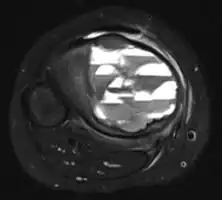

X-ray and CT scan show lytic expansion lesions with clear borders.[1] Expansion of cortex gives the lesion a balloon-like appearance. Larger lesions may appear septated.[10] MRI reveals fluid levels.[1] Bone scan shows outer radiotracer uptake, with a central dark area.[1]

MRI scan: showing fluid levels -